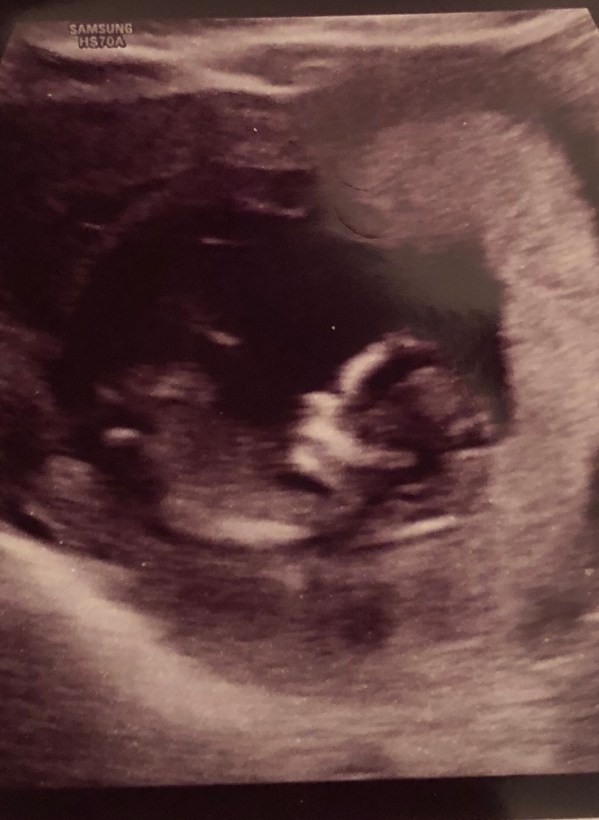

And ever since then, we just keep reminding ourselves of Faith over Fear. We saw baby C again on Adam’s birthday, growing so much already. (Have you ever seen a cuter nose??)

And just this past weekend, we found out our little bambino is a BOY! 💙 We are thrilled and can’t wait to meet him in August.